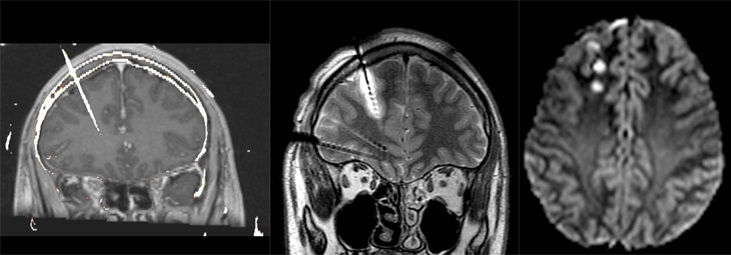

El sistema E-EEG consiste en colocar unos electrodos en zonas de la corteza cerebral para monitorizar la actividad eléctrica del cerebro. Después, con estos registros se elabora un mapa en tres dimensiones del foco epiléptico. Esto permite identificar la zona afectada para después tratarla mediante termocoagulación o tratamiento quirúrgico.

Antes de la cirugía o la termocoagulación, es importante encontrar el foco causante de las crisis epilépticas, y esto es posible con la nueva técnica de estéreo-electroencefalografía o E-EEG.

Este tratamiento usa de manera conjunta los electrodos profundos del sistema E-EEG y la técnica de termocoagulación para valorar la cirugía en personas con epilepsia refractaria, que, en algunos casos, no llega a ser necesaria.